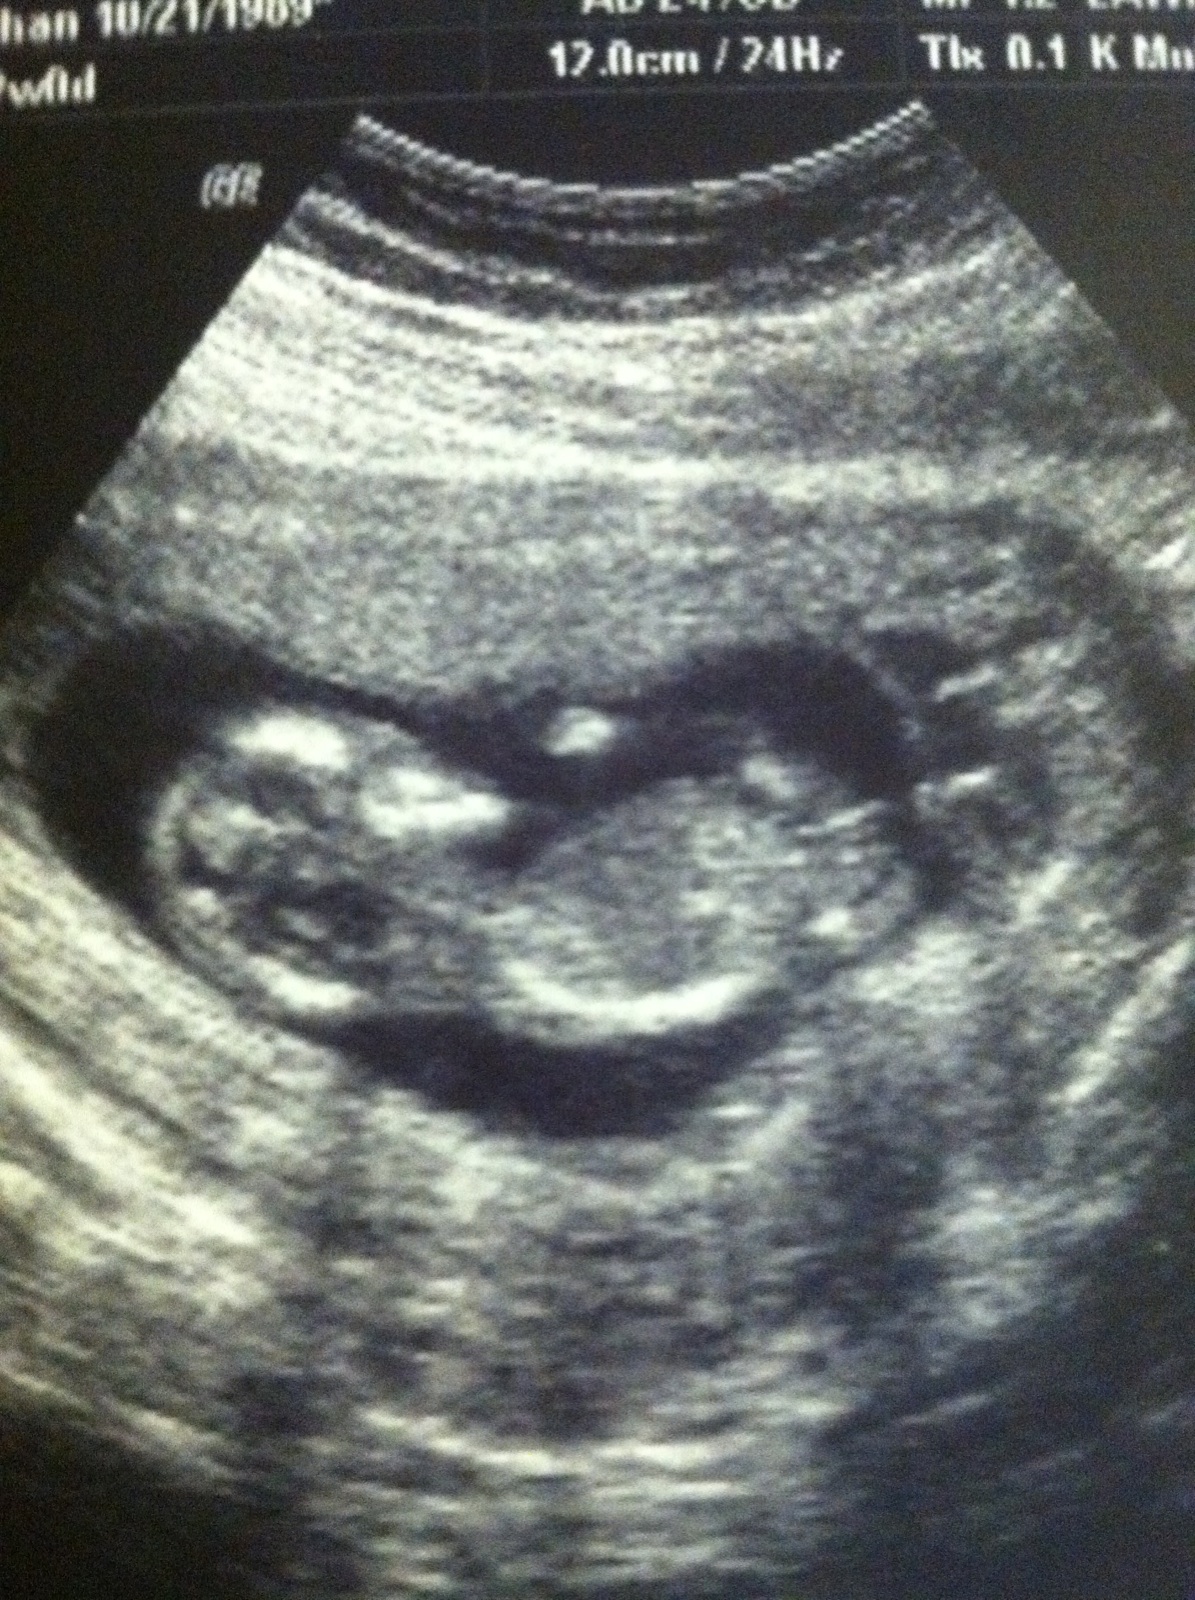

We won't find out the gender of the baby for another month but I'm dying to know!! Any guesses as to whether our little one is a boy or girl?? Nub theory guesses and skull theory guesses welcome!!

the nub isn't big or clear enough for me also your on the early side so im going to say a slight girl lean. i wouldn't be surprised either way though.

I know it's super early, I am just so anxious!! I made the picture bigger so hopefully that helps a little.